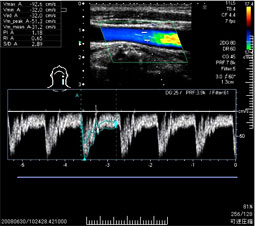

【エコー検査(超音波検査)】

頸動脈内部の血流測定    心臓の弁膜症の血流評価